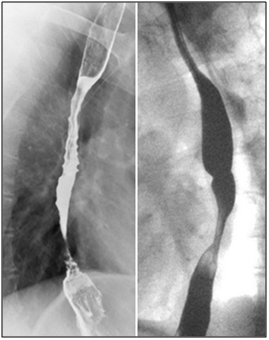

Symptoms recurred despite compliance with therapy and EGD two months later showed persistent LA Class D esophagitis without histologic evidence of opportunistic infection. A bariums wallow showed a tight 3cm long, 4 mm diameter stricture in the same location (Figure 2). Given the unusually refractory nature and mid-esophageal location of his circumferential esophagitis and stricture and no histologic evidence of Barrett’s, opportunists, or neoplasia, MMF was suspected to be the culprit. His MMF was discontinued and azathioprine was substituted. He was re-dilated to 12 mm using a through the scope (TTS) balloon. Barium swallow (Figure 3) at 3-month follow-up showed no evidence of esophagitis or stricture and PPI therapy was discontinued without symptomatic recurrence. At 2.5 year follow up he continues to be symptom free off of PPI therapy.

Figure 3 Normal barium swallow at 3 month follow-up.